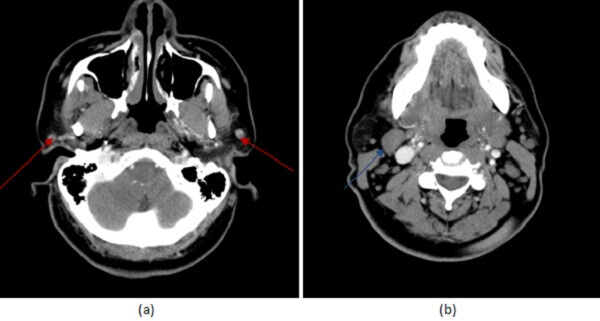

Figure 1: (a, red arrow) axial neck CT with contrast demonstrates small homogenously enhancing well circumscribed left parotid masses associated with an enlarged level 2 lymph node (b, blue arrow).

It is difficult to distinguish benign from malignant parotid masses based on imaging alone. Benign appearing lesions (such as in this case) can be malignant. Features suggestive of malignancy include ill defined borders, facial nerve paralysis, T2 signal and multifocality and lymphadenopathy. Ultrasound guided biopsy is often required to establish the diagnosis of a parotid mass.